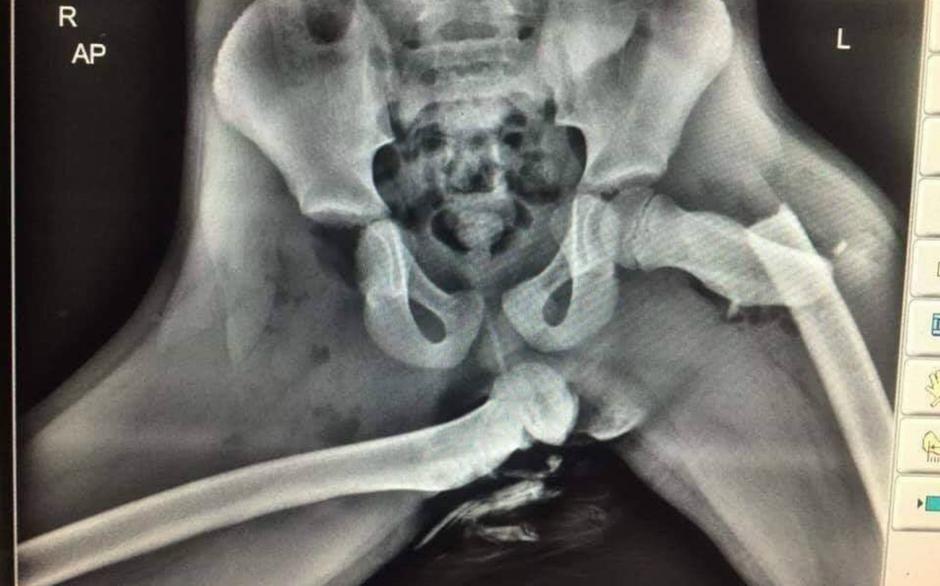

Rentgenski posnetek noge na armaturki | Avtor: Reševalni pas/Twitter Reševalni pas/Twitter

O tem, kako nevarno je, če sopotnik svoje noge položi na armaturno ploskev v avtu, priča ogromno dogodkov in nobeden se ni končal kaj prida lepo oziroma neboleče. Spodnji primer, ki je bil objavljen pred leti, je dokaz, kaj lahko telesu povzroči na videz nedolžna nesreča, če imamo noge uživaško položene na armaturni plošči. Sopotnikova desna noga je bila zaradi nesreče povsem iztaknjena iz kolka in je dobesedno predrla kožo. Sunek ob nesreči je bil tako močan, da je hkrati levo stegnenico grdo prelomilo.